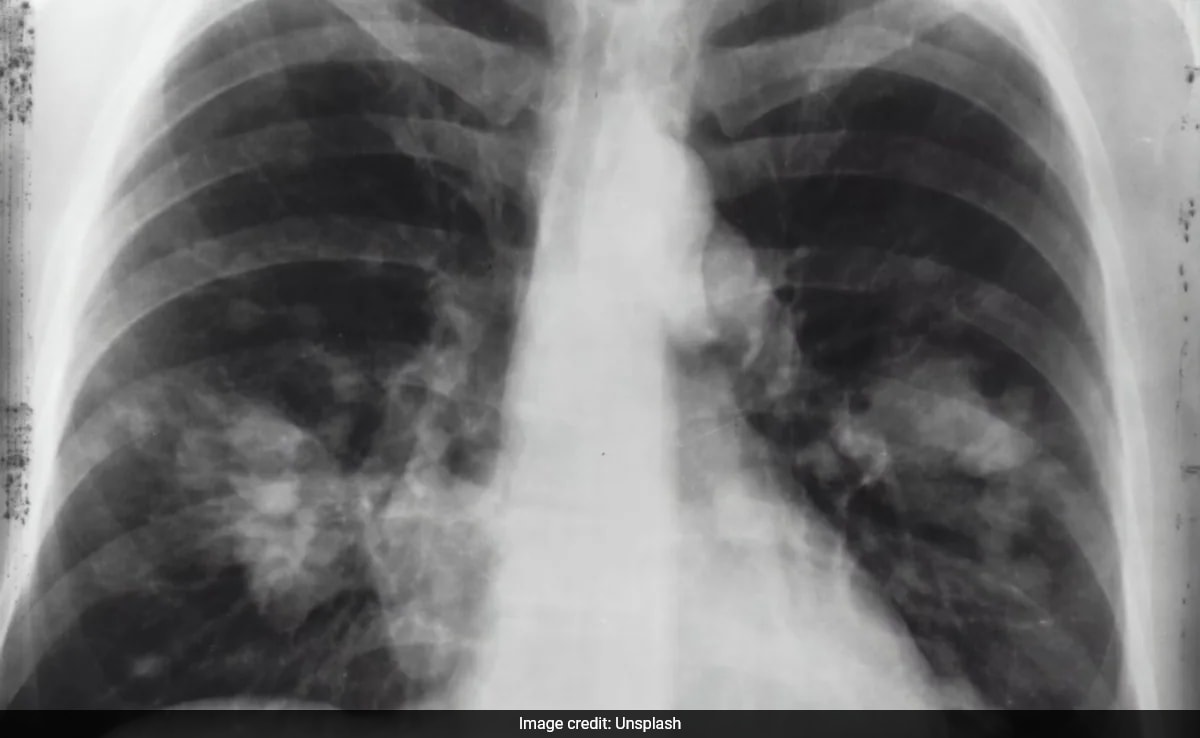

A study presented at the American Association for Cancer Research Annual Meeting 2024 found that accelerated aging, as indicated by biological age, is linked to an increased risk of early-onset cancers such as lung, gastrointestinal, and uterine cancers. The study suggests that interventions to slow biological aging could be a new avenue for cancer prevention, and screening efforts tailored to younger individuals showing signs of accelerated aging could help detect cancers early. However, the study's findings are limited to the UK population and need validation in diverse populations.